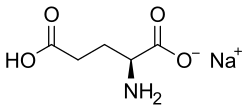

Cystine

Cystine is a dimer consisting of two cysteine molecules and the formation of a disulfide bond. This amino acid is a rate limiting substrate used in the SLC7A11 cystine/glutamate transporter and is usually imported into the cell. Cysteine-158 is specifically used in the formation of the disulfide bridge for the protein structure of system Xc-.[9] There are neurotoxins, such as BMAA, that can prevent the intake of cystine, which can lead to decreased extracellular glutamate levels and an increase in oxidative stress.[10]